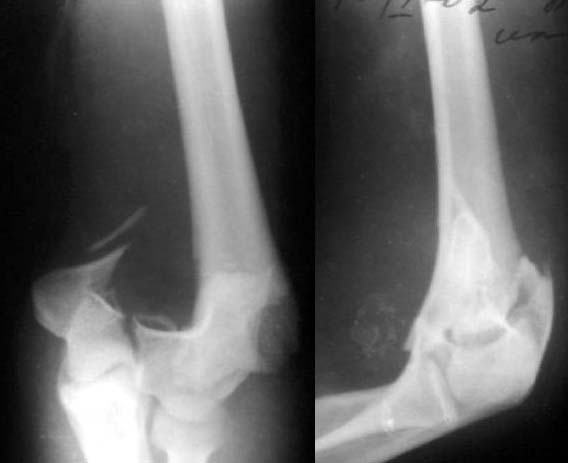

Все же открываться мы не стали. Результаты в приложении. Фронтальный снимок переделаю и пришлю еще раз. Мнения?

Кликните для загрузки файла k5.jpg